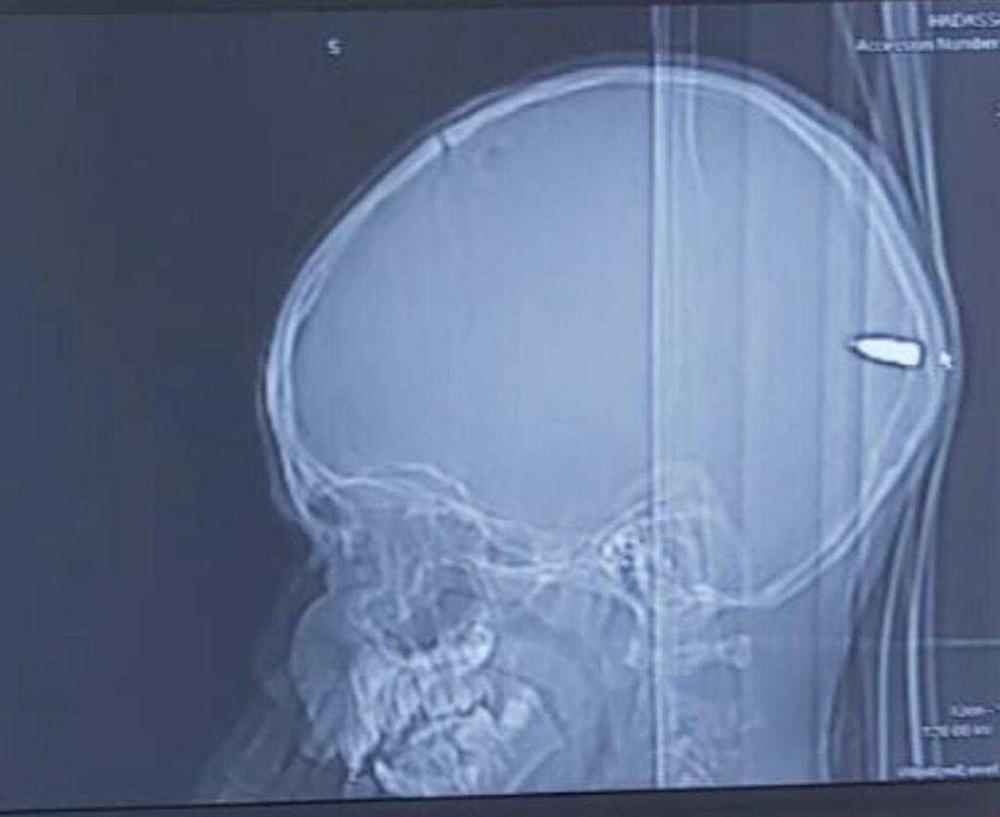

Lekari iz Jerusalima ostali su u šoku kada u otkrili što je uzrok iznenadne pospanosti kod devetogodišnjeg dečaka kojeg su zabrinuti roditelji doveli u bolnicu. Roditelji su s dečakom iz Palestine stigli u Medicinski centar Hadasah zato što je 9-godišnjak bio previše uspavan. Llekari su ga odmah pregledali, a na glavi su mu pronašli malenu ranu i krv u kosi. Odmah su mu uradili CT snimak nakon čega su otkrili kako dečak ima metak u glavi. Metak je prošao kroz lobanju i zaustavio se u dečakovom mozgu. Neurohirurg Gaj Elor koji je izvadio metak iz dečakove glave kaže kako roditelji nisu znali da je njihov sin pogođen.

– Majka je rekla da se igrao sa svojim prijateljima i da se nešto dogodilo, da je možda palo nešto na njega. Priča nije potpuno jasna. Imao je malenu ranu na glavi – ispričao je lekar, piše Tajms of Izrael. Sumnja se da je dečak pogođen tokom proslave Kurban-bajrama.

- Da je metak otišao u drugom smeru mogao je prouzrokovati mnogo veću štetu i značajno neurološko oštećenje – rekao je lekar i dodao kako se dečak dobro oporavlja i razgovara sa svojom porodicom.